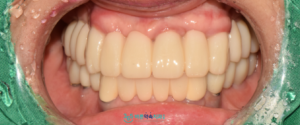

최종 보철물은

자연치아와 유사한 강도를

가지면서 우수한 지르코니아로 소재로

완성해 드렸습니다.

치료가 마무리된 후에는

양쪽으로 음식물을 저작하는 데

편안함을 느끼셨고,

웃는 모습도 훨씬 자연스러워졌다고

하시며 매우 만족해하셨습니다.